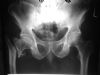

Hip Joint Ankylosis AP view - 50 Years post TB of the joint